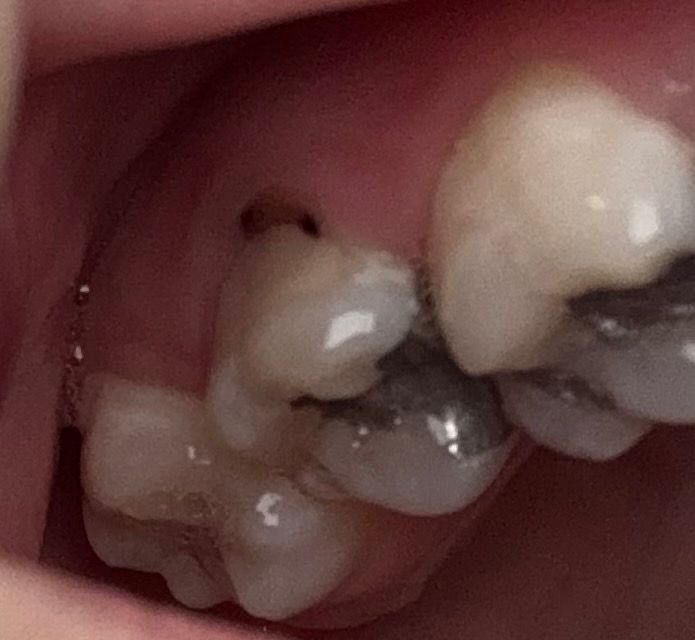

이랑 잇몸 사이에 검은색 이거 충치인가요

물마시거나 양치하거나 바람불면 치아가 시려웠어요.

잇몸하고 이가 이어지는 부분에 까만 무언가가 있네요....

안그래도 충치 잘 생겨서 진짜 열심히 양치하고 치실하고 있는데 이거 충치일까요ㅠㅠㅠ

만약 충치라면 얼마나 깊을까요 신경치료 가능성 있어보이나요??

사진만으로 진단을 내리기는 어렵습니다만 충치일 가능성이 있어보입니다. 치과 가보시는 게 좋겠습니다.

잇몸과 치아 경계부위에 충치가 잇는거 같습니다. 일단은 간단히 충치치료를 해야될것같지만 하고나서 시리거나 불편하면 신경치료를 하셔야될수도 잇습니다.

치경부마모와 함께 충치가 진행된 것 같습니다. 치아의 목 부위(치경부)는 신경쪽과 가깝기 때문에 조금 깊은 충치라고 하더라도 신경치료 가능성이 있습니다.

현재 충치로 의심이되며 충치의 깊이는 사진상으로 확인은 어렵기에 진료를 받길 권합니다.

가급적 빠른시일내에 치과에 방문하여 상태 확인후 치료를 진행하는 것이 충치의 진행을 막을수 있습니다.

사진으로 봤을 경우 단순한 착색일수도 있지만 충치의 가능성도 있어보입니다. 단순한 착색일 경우에는 간단하게 제거할수 있지만 충치라면 치료가 필요할수 있습니다.